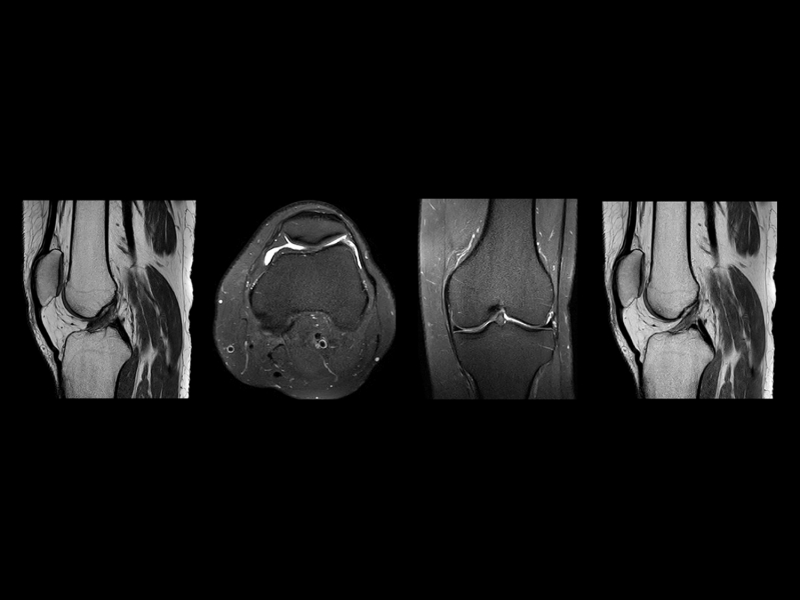

Mūsu klīnikā Teika Plaza, Rīgā, mēs piedāvājam dažādus magnētiskās rezonanses izmeklējumus gan valsts apmaksātus, gan privātus pakalpojumus. Mūsu pakalpojumi ir īpaši piemēroti neiroloģiskiem izmeklējumiem, locītavu izmeklējumiem, iekšējo orgānu analīzēm un daudzām citām diagnostiskām vajadzībām. Ar modernu iekārtu palīdzību mēs veicam izmeklējumus, kas nodrošina augstu precizitāti un atbilstību visām medicīniskajām prasībām.

Mūsu pakalpojumi aptver smadzeņu, mugurkaula, locītavu un iekšējo orgānu izmeklējumus. Mēs sniedzam detalizētus attēlus, kas palīdz ārstiem ātri noteikt diagnozi un izstrādāt efektīvas ārstēšanas metodes.

Mēs izmantojam Philips MR 5300 1.5T sistēmu, kas sniedz visaugstāko kvalitāti un precizitāti magnētiskās rezonanses izmeklējumos. Mūsu tehnoloģija nodrošina ātrus izmeklējumus un precīzus rezultātus, kas palīdz ārstiem pieņemt pareizus lēmumus.